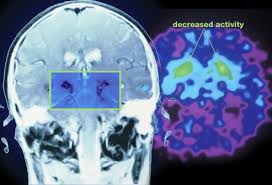

این اختلال هنگام رخ می دهد که نواحی خاصی از مغز توانایی خود در تولید دوپامین (یکی از ناقلین عصبی در مغز) را از دست می دهند.

بعد از آلزایمر، پارکینسون شایعترین بیماری مخرب اعصاب به حساب میآید پارکینسون بیماری مزمن و پیشروندهای است که در آن سلولهای ترشحکننده دوپامین در جسم سیاه در مغز میمیرند و در فقدان دوپامین حرکات بدن نامنظم می شود.